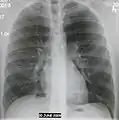

A chest X-ray showing a very prominent wedge-shape bacterial pneumonia in the right lung | |